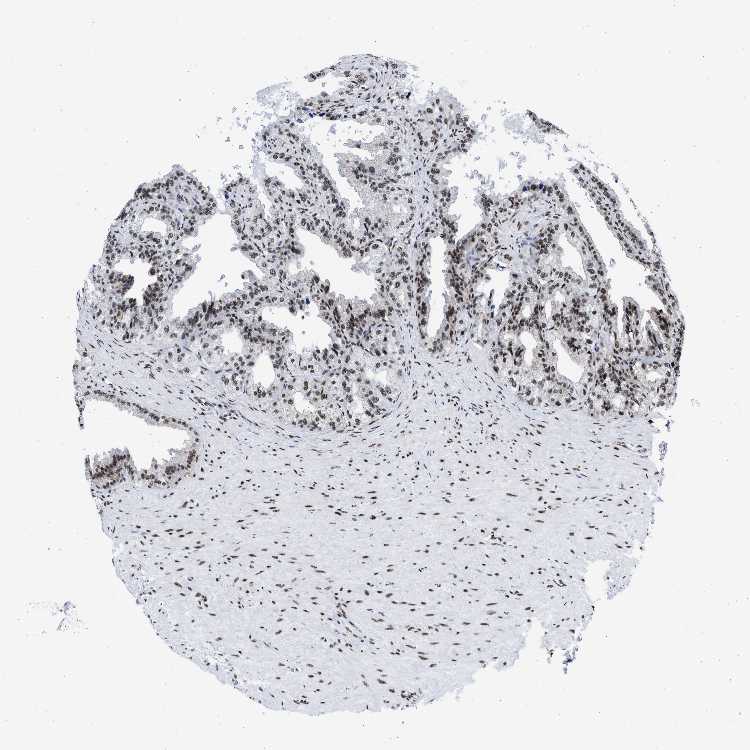

SEMINAL VESICLE - Antibody stainingi

Antibody staining in the annotated cell types in the current human tissue is reported as not detected, low, medium, or high, based on conventional immunohistochemistry profiling in selected tissues. This score is based on the combination of the staining intensity and fraction of stained cells.

Each image is clickable and will lead to virtual microscopy that enables deeper exploration of all samples and also displays staining intensity scores, fraction scores and subcellular localization as well as patient and tissue information for each sample.

Antibody HPA018403

Glandular cells Medium